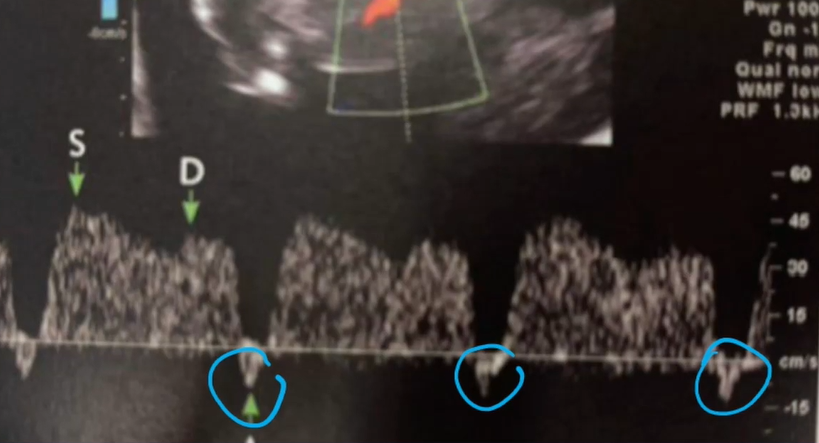

Como é a onda A reversa no USG doppler? O que ela indica?

A

Indica maiores chances de cromossomopatia e malformação cardíaca